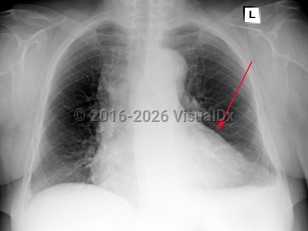

Pulmonary embolismPulmonary embolism